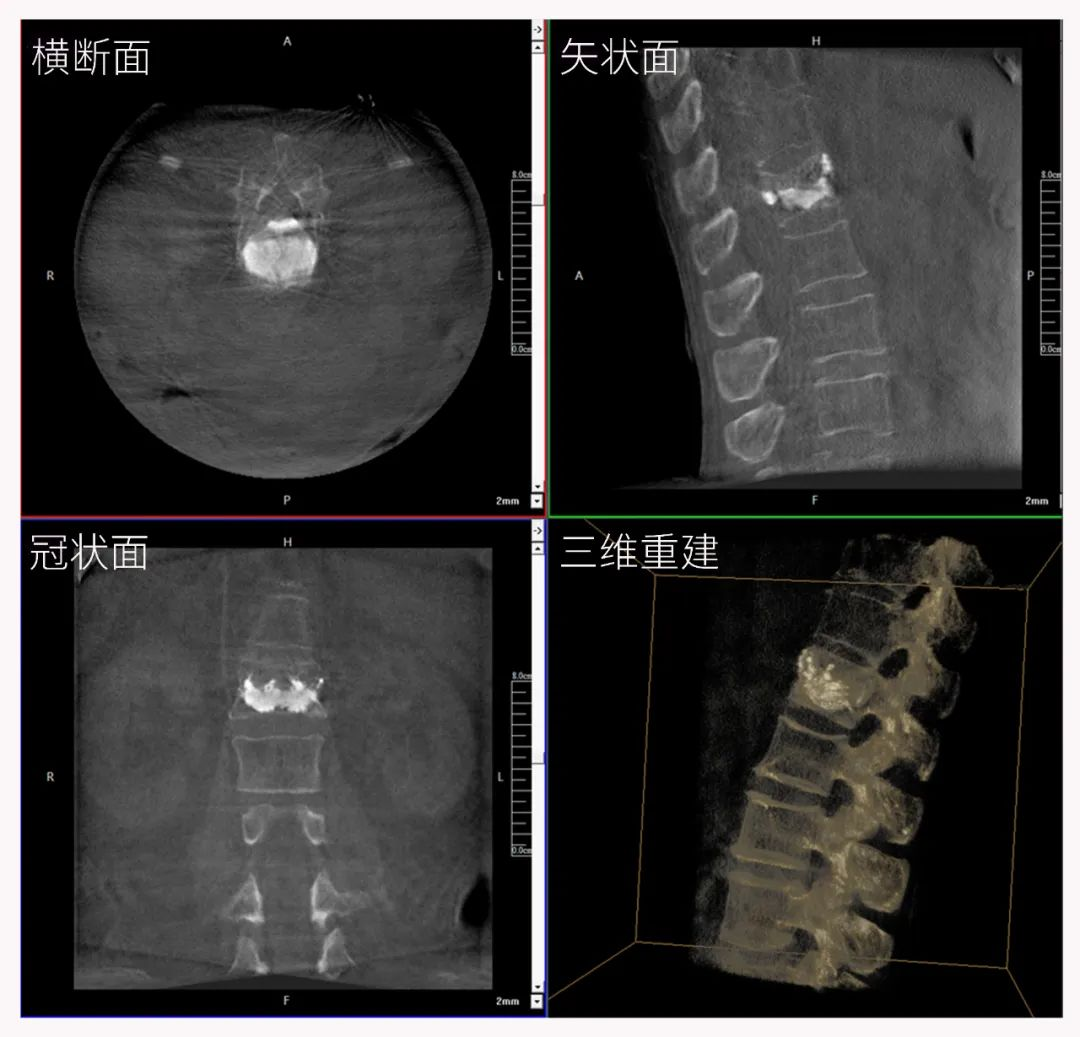

三維C形臂也被稱為“術(shù)中CT”,它具備二維C形臂的全部功能。此外,它還具備三維成像功能,三維C形臂旋轉(zhuǎn)采集多角度的二維投影數(shù)據(jù),再通過計(jì)算機(jī)進(jìn)行三維重建,能夠生成橫斷面、矢狀面、冠狀面斷層圖像以及三維立體圖像,提供更全面、更立體的解剖學(xué)信息。

在臨床使用中,三維C形臂能看到二維影像所觀察不到的信息:

二維C形臂提供的影像存在固有局限性,其成像原理是基于單一方位的投影,導(dǎo)致深部解剖結(jié)構(gòu)信息缺失,且容易受到骨骼和組織的重疊干擾,使得部分病灶難以清晰顯示,甚至被掩蓋。相比之下,三維C形臂通過三維重建技術(shù),可以獲得類似CT的斷層掃描圖像,從而解決了二維影像的重疊問題。

醫(yī)生能夠利用這些三維圖像,更直觀、更深入地分析病變,進(jìn)行全方位觀察,例如:精確評(píng)估骨折復(fù)位情況、清晰顯示內(nèi)植入物的位置及其與周圍組織的關(guān)系等。尤其在復(fù)雜骨折、脊柱手術(shù)、呼吸介入等臨床場(chǎng)景中,三維C形臂提供的詳細(xì)信息對(duì)手術(shù)導(dǎo)航和療效評(píng)估至關(guān)重要。